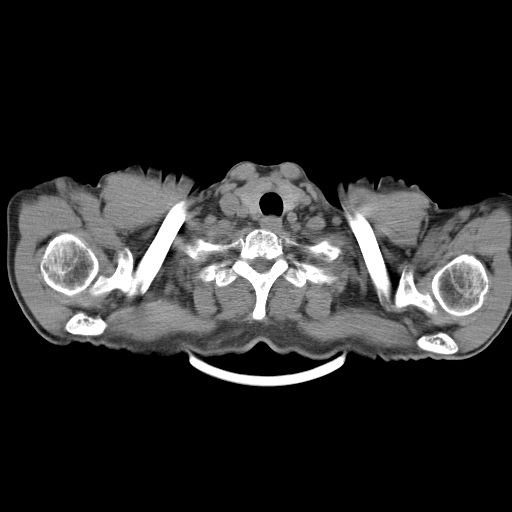

以下是引用shuiyuan在2010-3-1 10:45:00的发言:[br]考虑左肺上叶中心型肺癌伴阻塞型炎症,邻近胸膜受侵。

以下是引用心路寻觅在2010-3-1 10:23:00的发言:[br]1、考虑左肺上叶周围型肺癌[br]2、右上肺陈旧性病灶。[br][br][本贴已被 心路寻觅 于 2010-3-1 10:40:18 修改过]